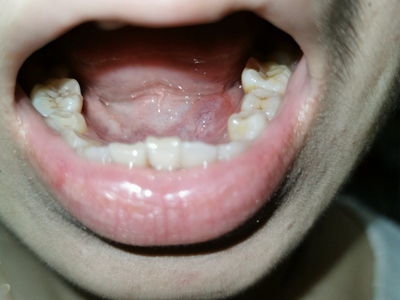

舌下腺囊肿舌头下长一个圆形肿物图

舌下腺囊肿可以发生在小孩舌头下面,表现为一个半圆形的囊肿,看上去像有两个舌头,摸起来质地软而有弹性,进食时会有疼痛不适感,进食后可缓解。